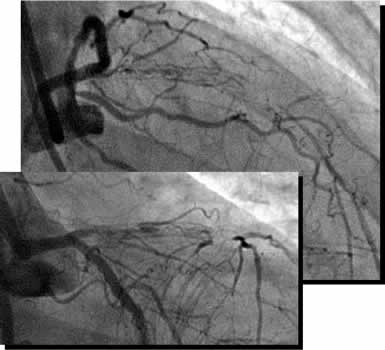

| Final CAG Findings:'01.9.5 LVG: asynergy (A), EF: 71% CAG: #6 90% (ISR) #7 CTO (collateral from RCA) |

I-3 : months follow-up angio